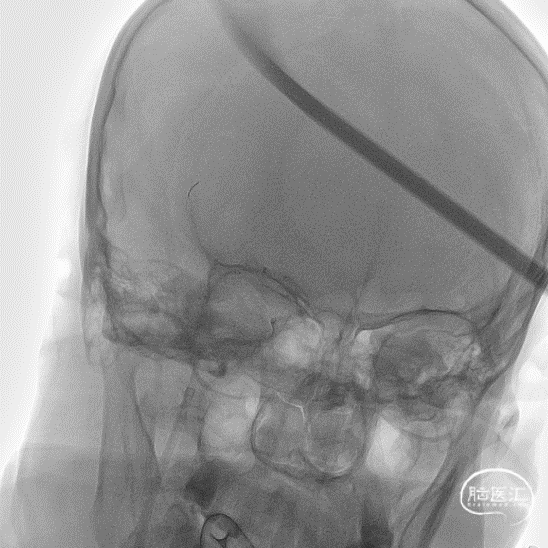

术前造影提示右侧大脑中动脉下干闭塞。

使用8F导引导管在6F 125cm Tethys®中间导引导管同轴下超选至右侧颈内动脉建立通路,造影可见右侧大脑中动脉M1下干闭塞。